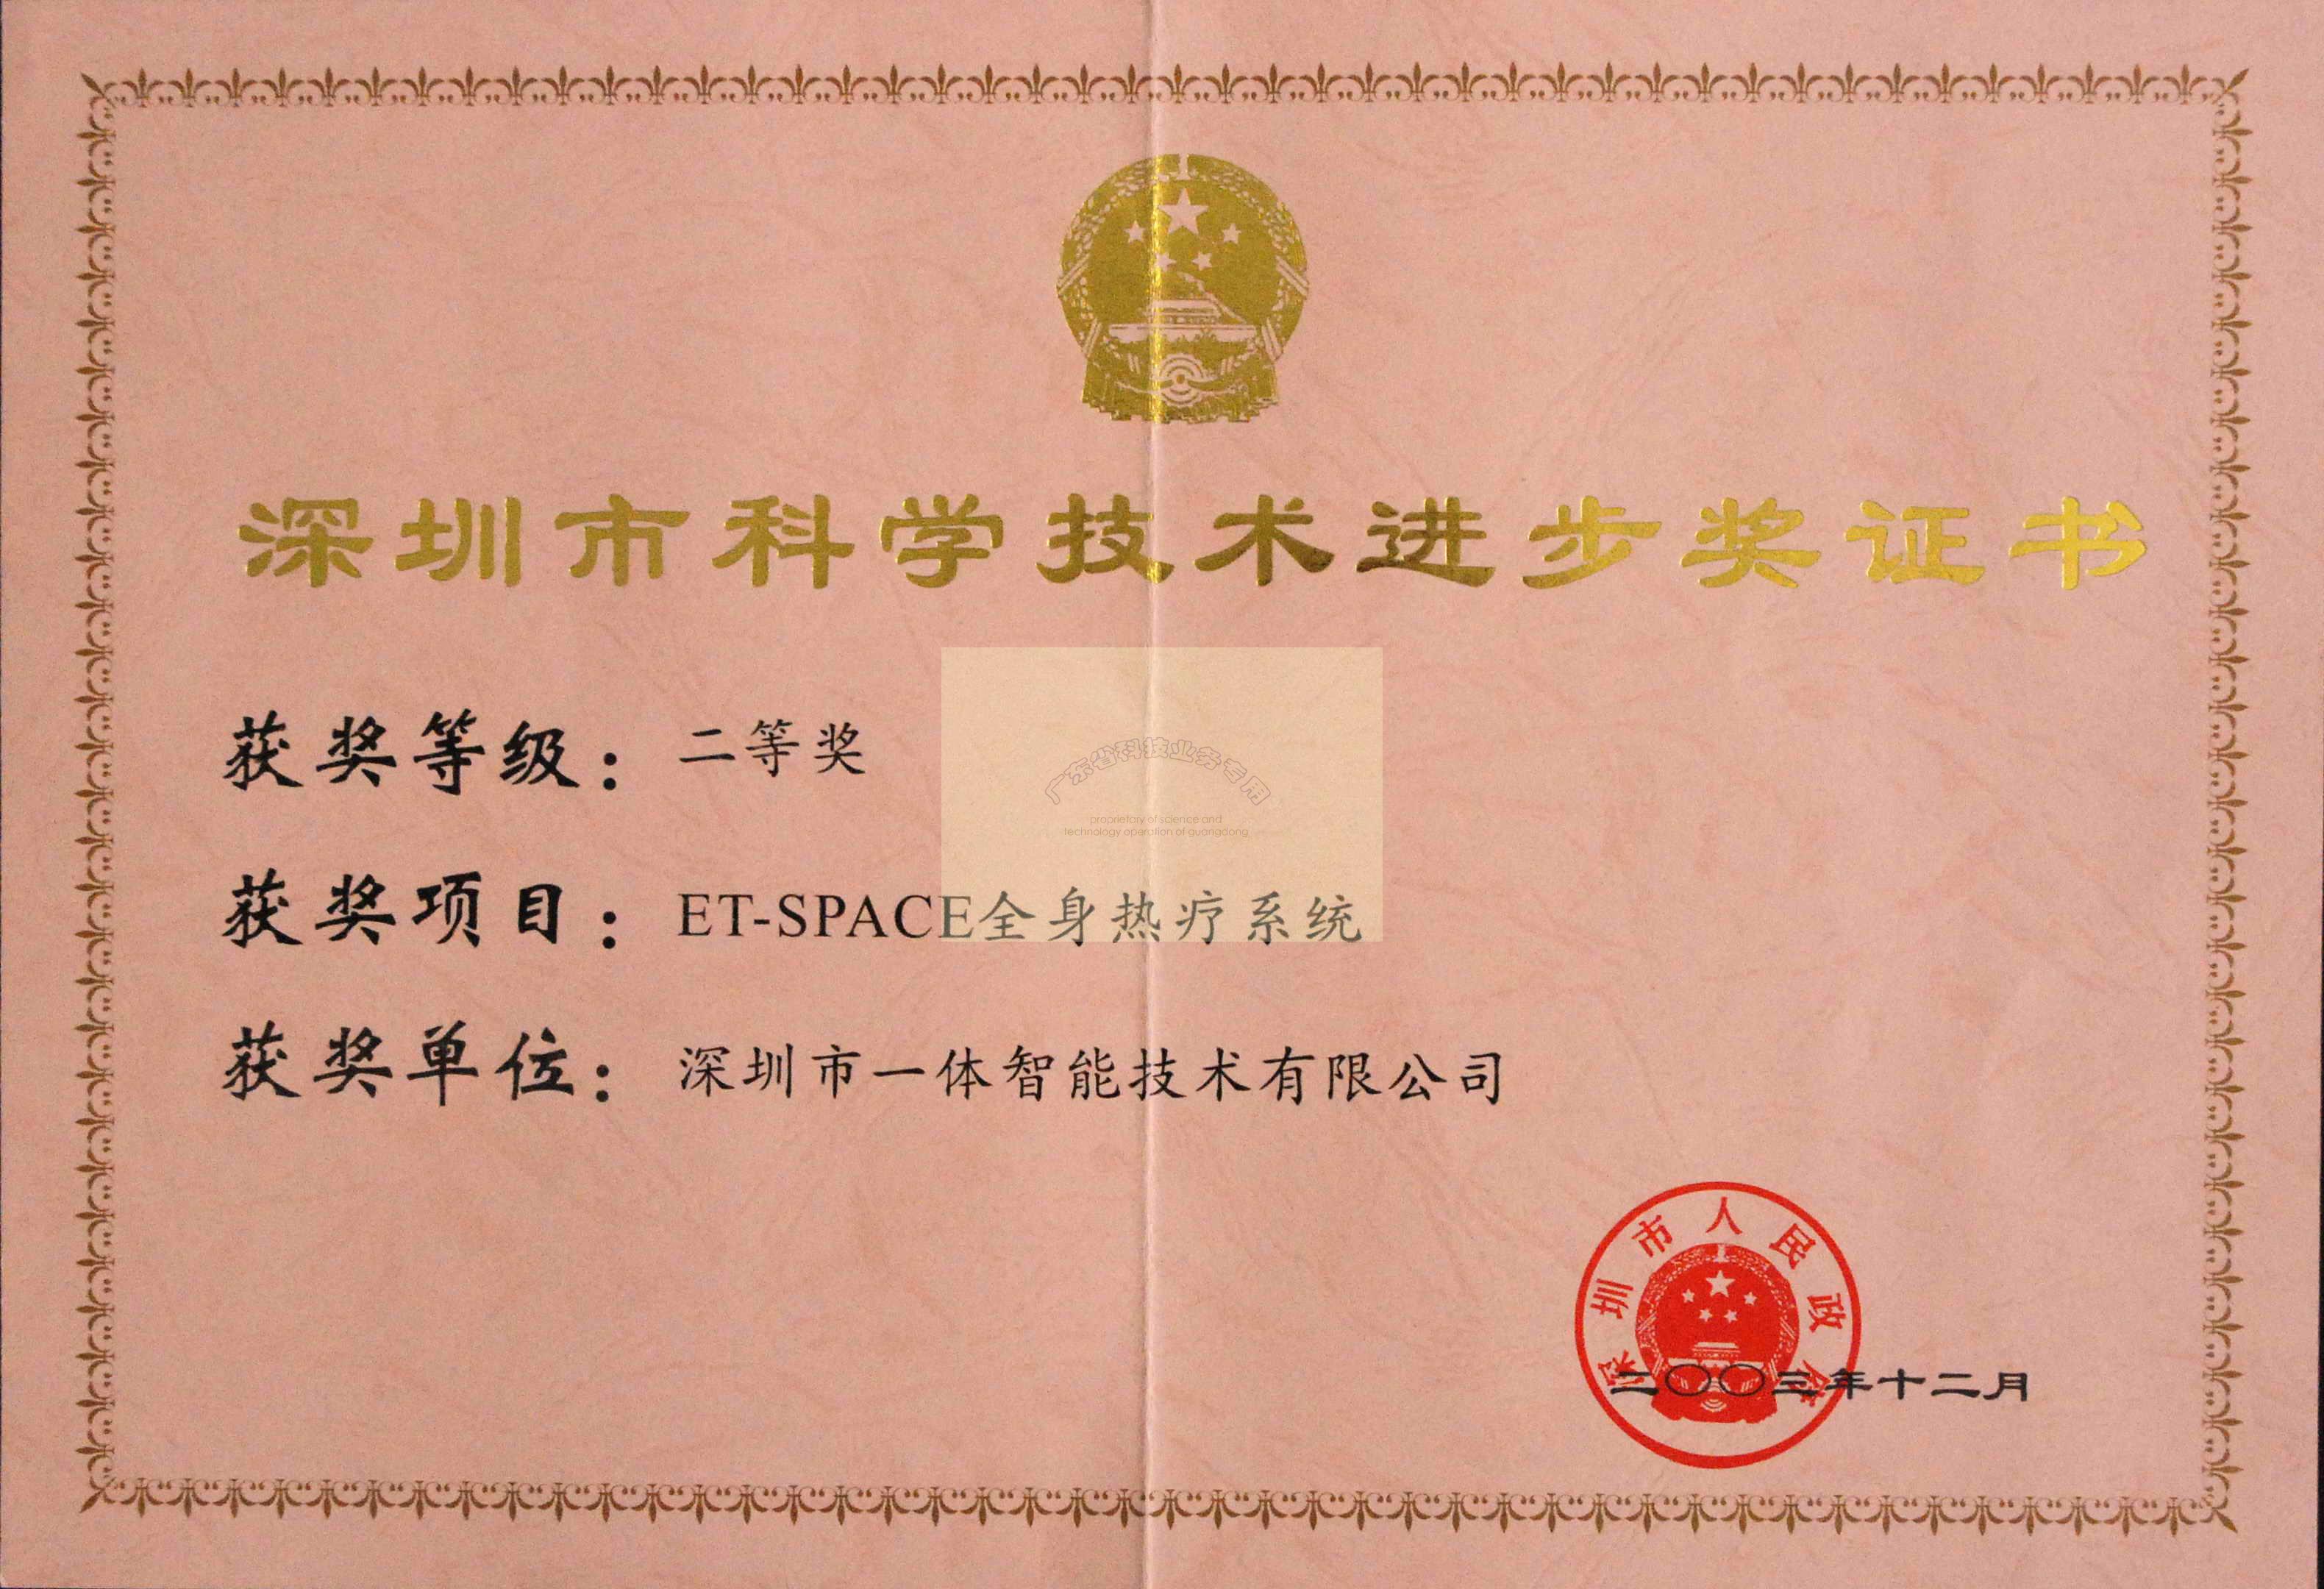

ж·ұеңіеёӮ科еӯҰжҠҖжңҜеүҚиҝӣдәҢзӯүеҘ–